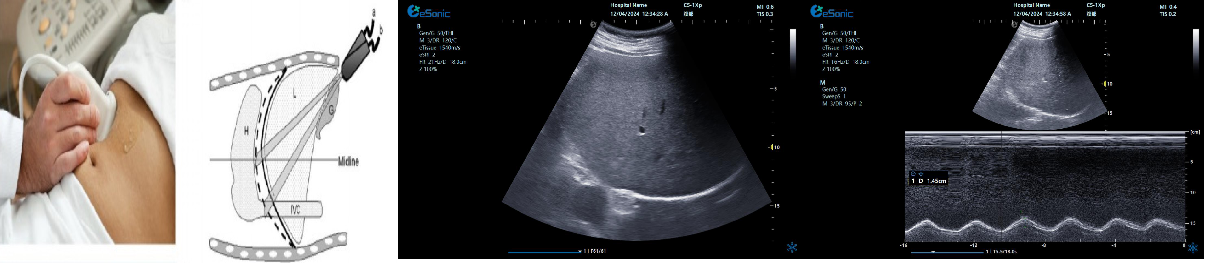

膈肌超

评估内容:膈肌移动度、膈肌厚度、增厚率。

评估意义:判断病人膈肌功能,呼吸功能,脱机前后评估等

常用检查模式:B、M

检查探头:凸阵、线阵

对超声设备要求:M型、解剖M型;测量快速准确;有专用的测量包

膈肌厚度检查

image.png

探头:高频线阵探头

部位:放置于腋前线与腋中线,7/8肋间或8/9肋间,沿肋间隙放置,观察和测量膈肌的厚度。

功能:M型超声,膈肌测量包

膈肌厚度变化

膈肌厚度测量

呼气末膈肌厚度正常值为2.0-3.5cm

膈肌活动度检查

探头:低频探头

部位:放置在腋前线或锁骨中线与肋缘交界处,启用M模式取样线垂直于膈肌,观察和测量膈肌运动幅度。

功能:M超,膈肌测量包

膈肌活动度测量